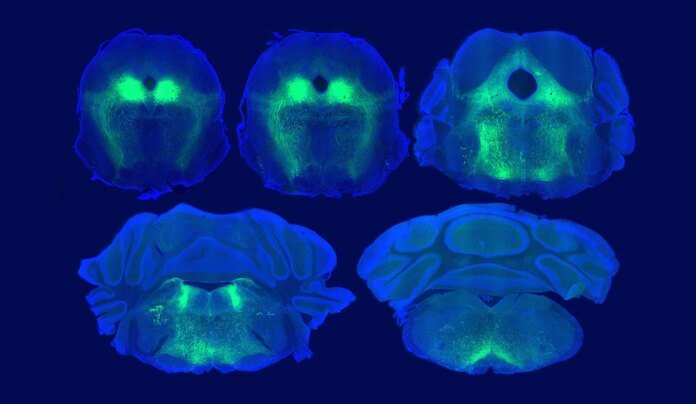

Ein weiterer Test zeigte, dass die Wirkung wirklich auf körpereigenen Opioiden beruhte: Verabreichten die Forschenden den Mäusen das Medikament Naloxon, das Opioidrezeptoren blockiert, blieb die Placebo-Schmerzlinderung vollständig aus. Zusätzliche Analysen enthüllten die verantwortliche Hirnregion: Entscheidend ist demnach die Signalübertragung im sogenannten ventrolateralen periaquäduktalen Grau (vlPAG). Diese Region bildet eine Art Schaltstelle zwischen Signalen aus dem Großhirn, dem Hirnstamm und dem Rückenmark und wurde bereits früher mit der Schmerzverarbeitung in Verbindung gebracht. In dieser Hirnregion entfalten injizierte Opioide ihre Wirkung und genau hier werden auch durch den Placebo-Effekt körpereigene Endorphine ausgeschüttet.